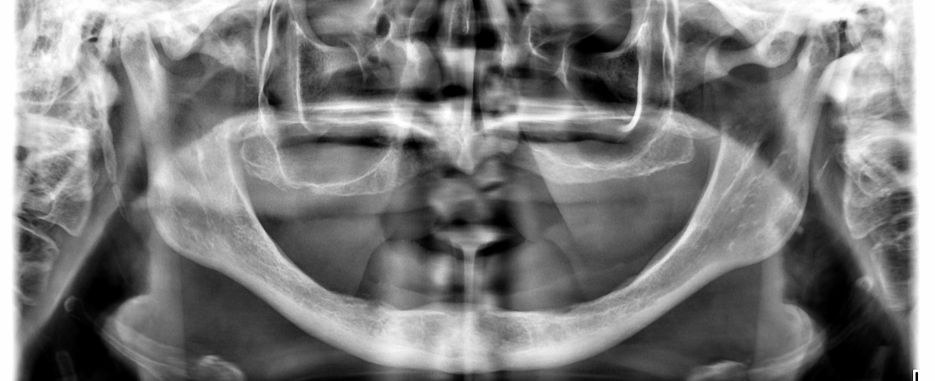

El proceso más adecuado para lograr un implante dental exitoso es el injerto óseo. Una vez que se estudia el caso del paciente, se realiza este procedimiento para lograr elevar el suelo del seno maxilar. Esto permite implantar una nueva pieza, garantizándose un buen resultado.

El especialista puede elegir colocar implantes de carga inmediata de manera provisional, hasta que la pieza definitiva esté disponible y sea afín a las necesidades del paciente. Ante cualquier intervención, se puede realizar una cirugía periapical, que facilite una perfecta regeneración ósea, extirpando cualquier lesión en la raíz de la pieza dental.